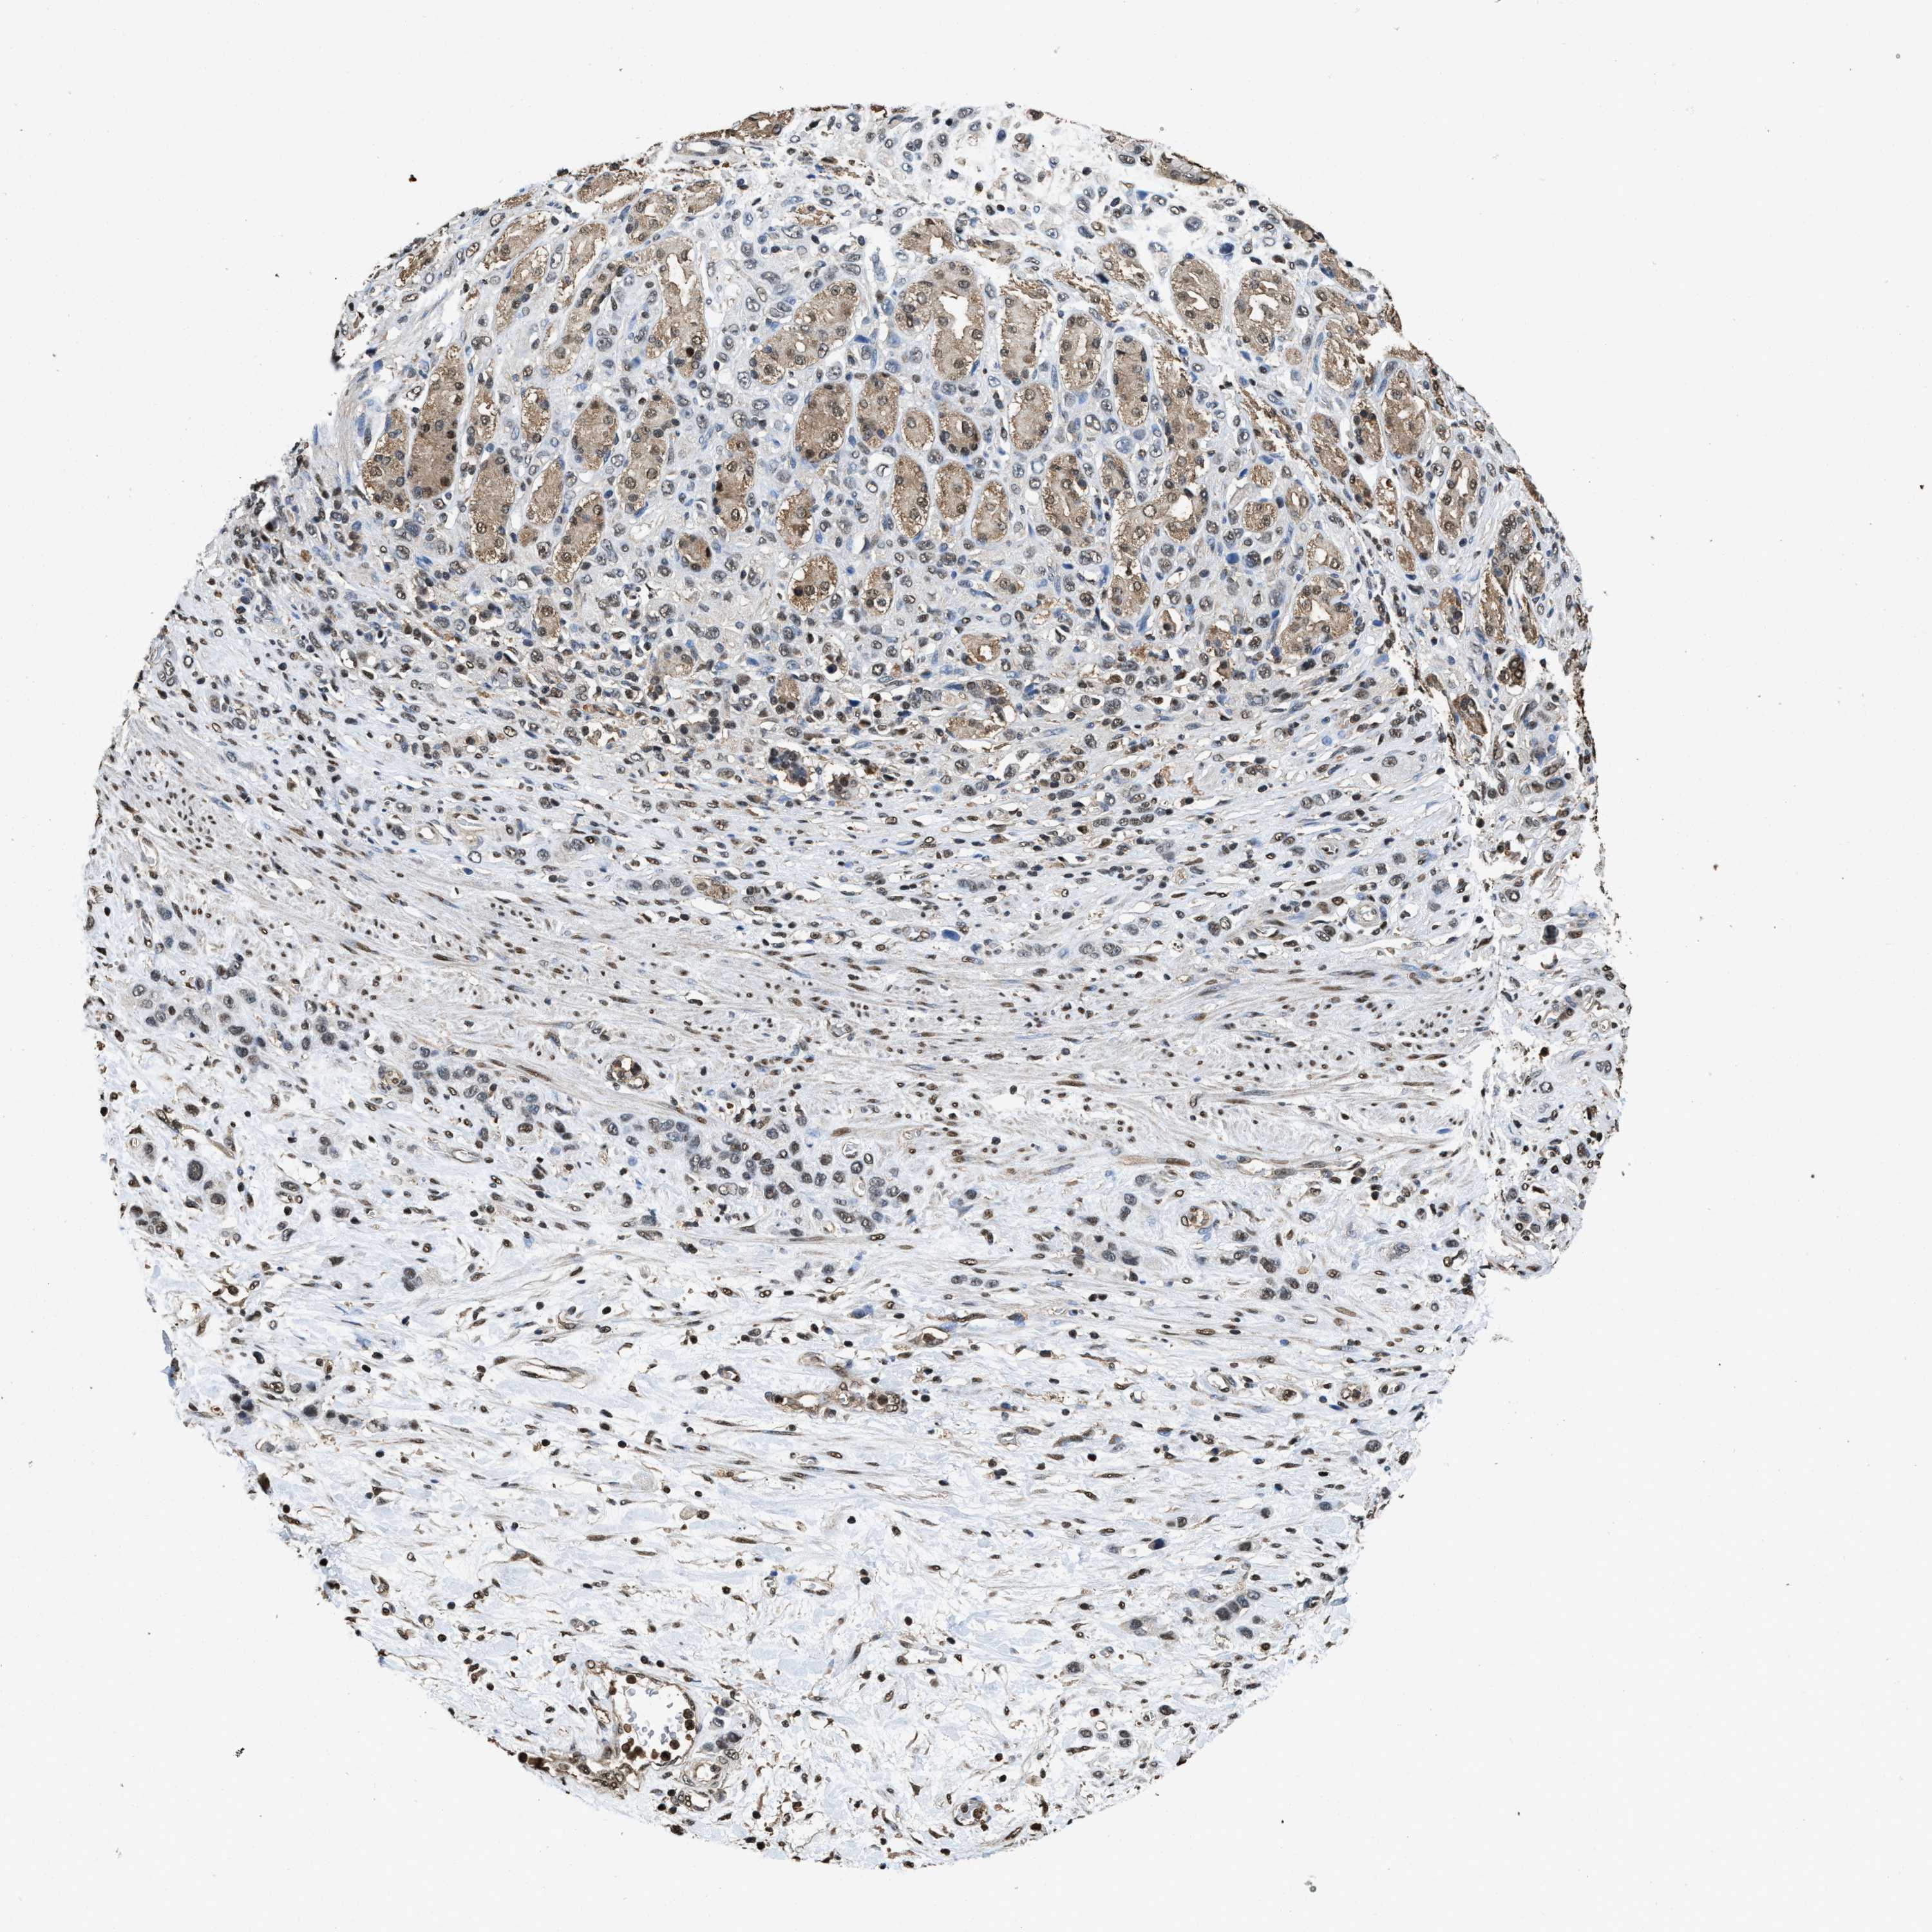

STOMACH CANCER - Protein expressioni

A mouse-over function shows sample information and annotation data. Click on an image to view it in a full screen mode. Samples can be filtered based on level of antibody staining by selecting one or several of the following categories: high, medium, low and not detected. The assay and annotation is described here.

Note that samples used for immunohistochemistry by the Human Protein Atlas do not correspond to samples in the TCGA dataset.

Antibody stainingi

Antibody staining in the annotated cell types in the current human tissue is reported as not detected, low, medium, or high, based on conventional immunohistochemistry profiling in selected tissues. This score is based on the combination of the staining intensity and fraction of stained cells.

Each image is clickable and will lead to virtual microscopy that enables deeper exploration of all samples and also displays staining intensity scores, fraction scores and subcellular localization as well as patient and tissue information for each sample.

Staining

High

Medium

Low

Not detected

Intensity

Strong

Moderate

Weak

Negative

Quantity

>75%

75%-25%

<25%

None

Location

Nuclear

Cytoplasmic/membranous

Cytoplasmic/membranous,nuclear

Adenocarcinoma, NOS

Adenocarcinoma, High grade